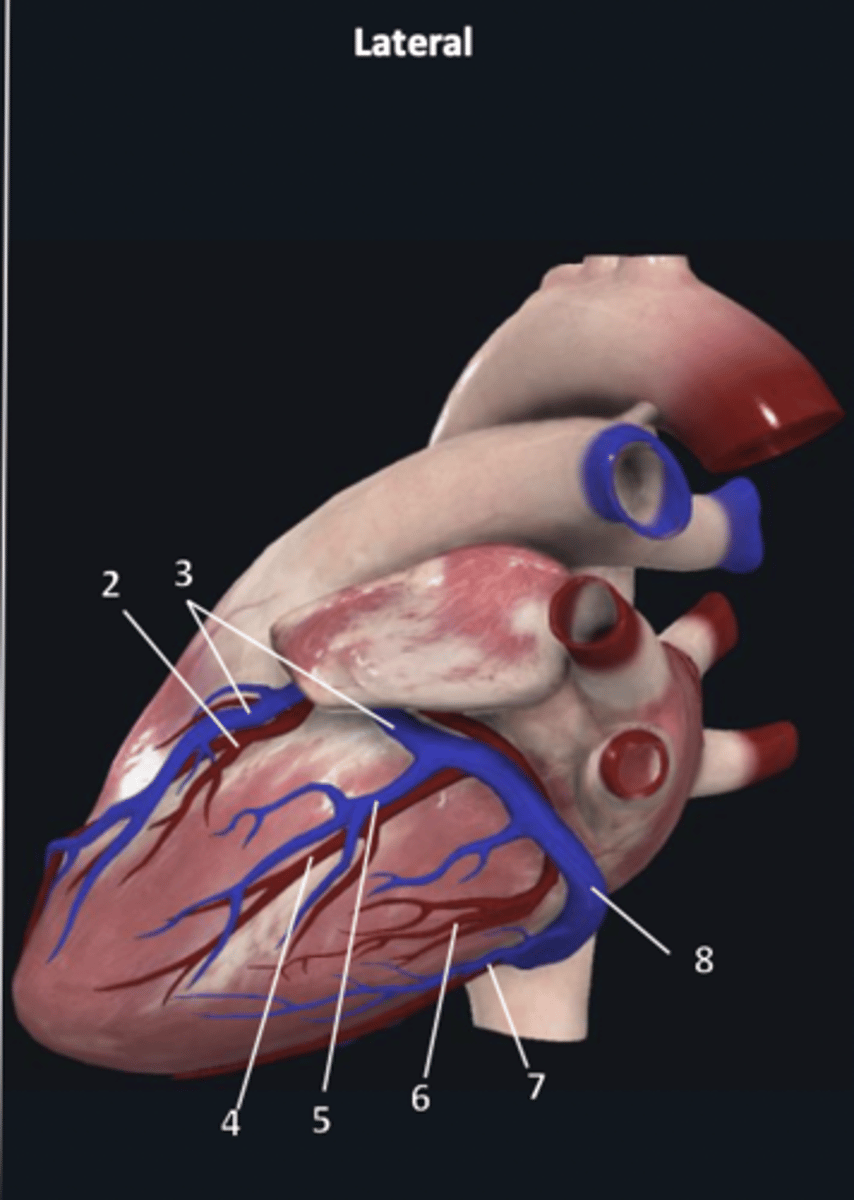

right coronary artery

1

anterior interventricular artery

2 (red)

great cardiac vein

3 (blue)

anterior interventricular artery

2 (red)

great cardiac vein

3 (blue)

left marginal artery

4

left marginal vein

5

posterior left ventricular artery

6

posterior vein of left ventricle

7

coronary sinus

8